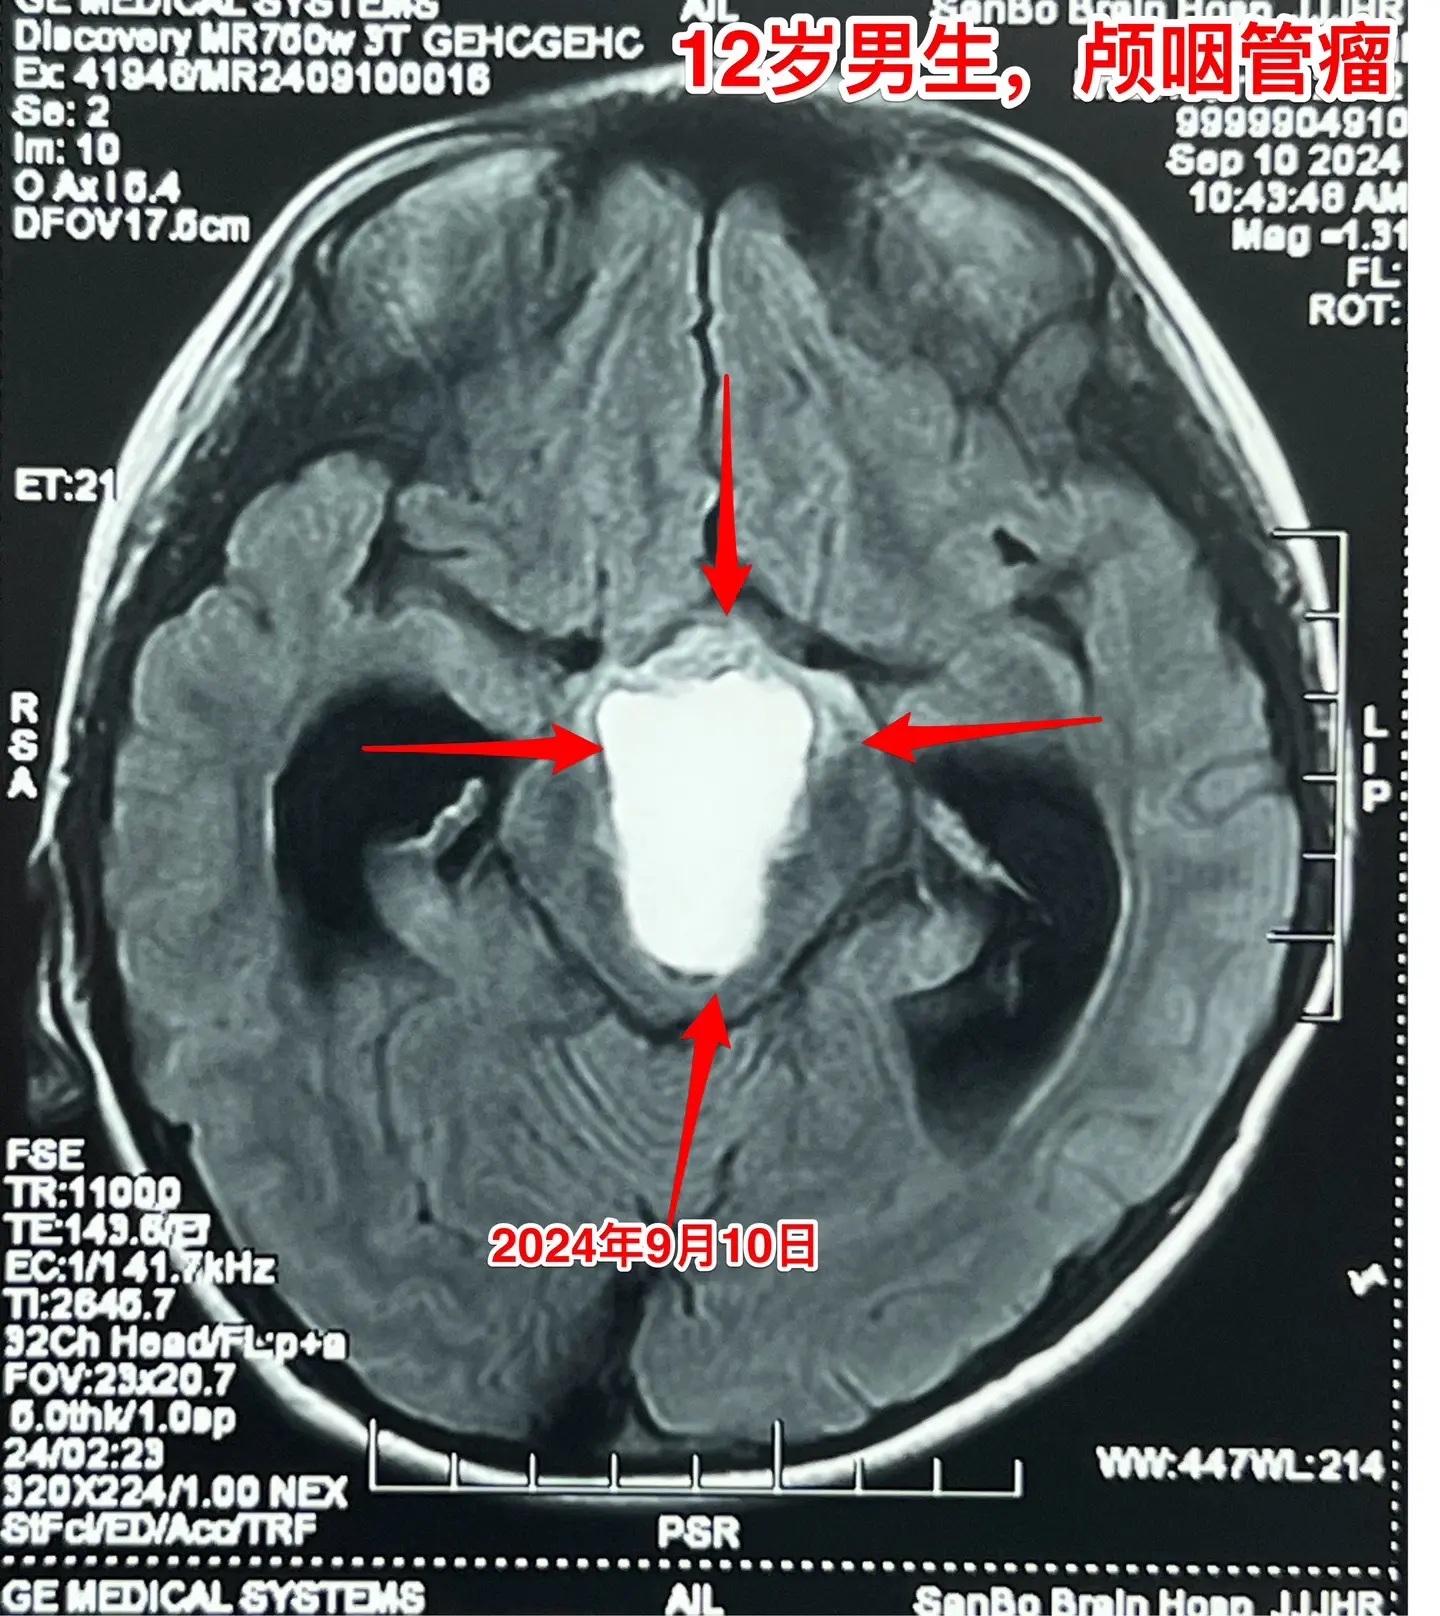

12岁南京男孩子头痛、呕吐。平时感觉身体很好,9月7日因头痛、呕吐到医院检查发现脑部长了颅咽管瘤,并且有脑积水。 9月9日到我院住院。住院时头痛、呕吐症状减轻了。复查磁共振显示颅咽管瘤的形态稍有变化,脑积水似乎有减轻。测视力发现他的视力有下降。这个颅咽管瘤生长的时间预计有两年时间,患儿症状不严重,最终因脑积水出现头痛、呕吐症状才发病。仔细检查还是可以发现一些蛛丝马迹,比如视力下降。颅咽管瘤有时会自动变小,很可能是肿瘤囊破裂了。囊变小了,脑积水就减轻了,头痛、呕吐症状就减轻了。 9月19日行开颅手术,将颅咽管瘤完全切除。手术后患者感觉视力有好转。希望肿瘤永不复发。